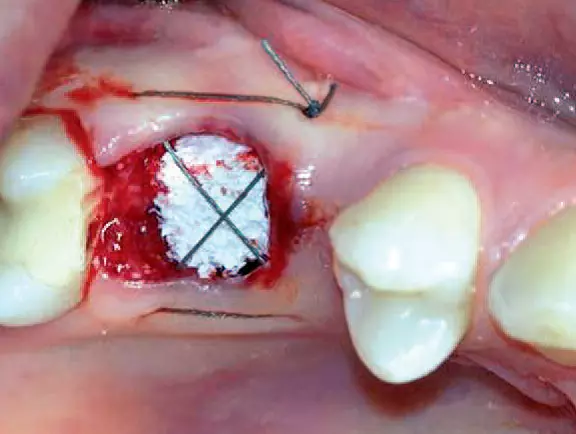

Augmentation

Trotz der schlechten, hart- und weichgewebigen Grundvoraussetzungen konnte der Kieferkamm zufriedenstellend rekonstruiert werden. Die Augmentation des kombinierten, horizontalen und vertikalen Defekts mit Yxoss CBR®, Geistlich Bio-Oss®, Geistlich Bio-Gide®, autologem Knochen und PRF ermöglichte die Implantation mit hoher Primärstabilität in den rekonstruierten Bereich.